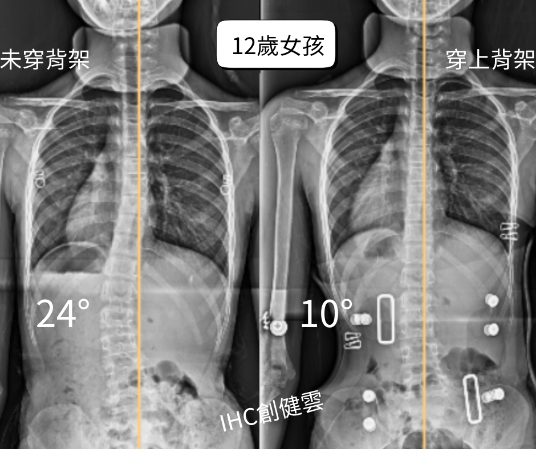

12歲脊椎側彎女孩,腰彎24度

這位12歲的女孩,經醫師轉介來製作【施羅斯側彎矯正背架】。

穿上背架後,立即矯正效果: 腰彎由24度→10度!

整體身形更筆直,體態平衡明顯回正。